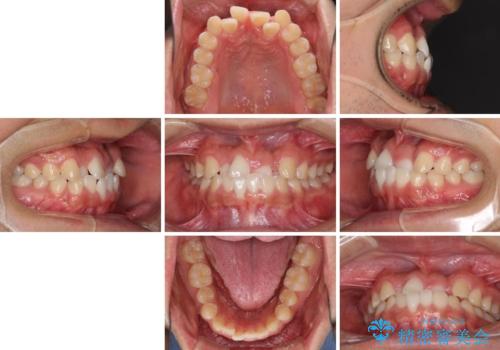

- 前歯のクロスバイトを気にして来院された患者様です。

美容専門の歯科医院を受診したところ、セラミックでの改善は無理と断られてしまったとのことでした。

歯がすり減って不揃いの形態となっていますが、まずは矯正治療によりクロスバイトを改善することとしました。

治療期間を極力短くしたいとのことで、ワイヤー矯正により治療を行うこととしました。

今後はすり減ってしまった歯の形をセラミッククラウンで改善したいとのことで、クロスバイトが改善し咬みやすくなった時点で装置を外すこととしました。

1年で治療を終えることができ、患者様には大変満足していただきました。